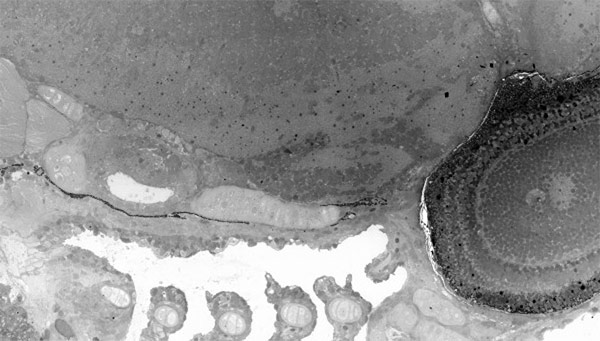

میکروسکوپهای الکترونی میتوانند نقشههای بسیار دقیق و حتی سه بعدی از ساختار اجزای سلولها تهیه کنند. اما به قیمت از دست دادن تصویر بزرگتر. حال دانشمندان دانشگاه Leiden هلند به تکنولوژیای به نام نانوسکوپی مجازی دست یافتهاند که امکان مشاهده کلی سلول و همچنین اجزای آن را در یک عکس واحد میدهد. برای این کار، آنها ابتدا چند تصویر نمونه مورد آزمایش را با رزولوشن نانومتری به هم پیوند زدند تا نقشهای با قابلیت زوم تهیه کنند. تحقیق آنها منجر به عکس 281 گیگاپیکسلی (با 16 میلیون پیکسل در اینچ) از جنین 1.5 میلی متری یک گونه جانور آبزی به نام گورخر ماهی شد.